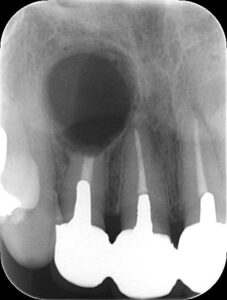

歯科用CBCT(X線撮影装置)による3次元解析

従来の平面的なレントゲンでは、サイナストラクトの原因となる病巣の広がりや、根管の複雑な構造を把握することは困難でした。

当院では歯科用CBCTを使用し、病巣の大きさ、骨の破壊具合、サイナストラクトがどこから伸びているのかを立体的に確認します。

これにより、再治療が必要な根管をピンポイントで特定できます。